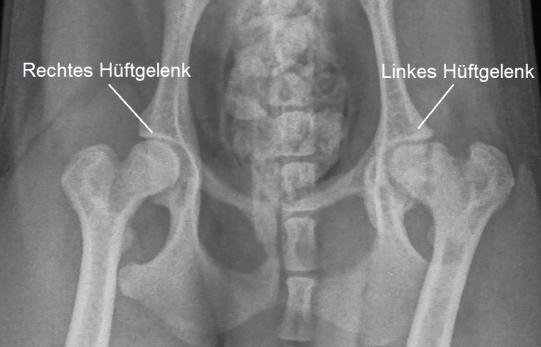

Im Untersuch scheint die Hüftregion des Junghundes schmerzhaft. Die Ursache dafür ist in einem Röntgenbild klar ersichtlich: Der linke Oberschenkelkopf escheint stark verändert; er ist nicht wie sein rechtes Gegenstück schön rund, sondern etwas eckig und von verminderter Röntgendichte. Mero leidet an einer sogenannten Aseptischen Femurkopfnekrose (Morbus Legg-Calvé-Perthes).